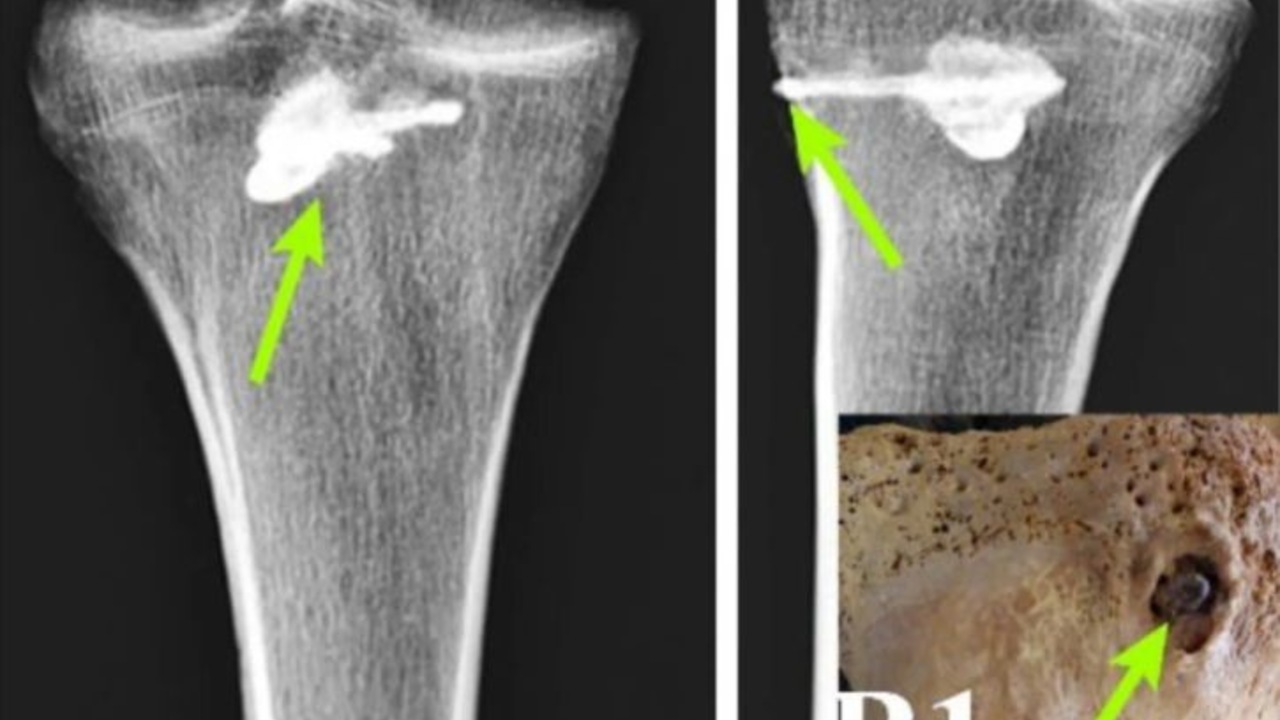

Погребённый лежал на левом боку с согнутыми ногами. В правой большеберцовой кости сохранился трёхлопастный металлический наконечник длиной 44 миллиметра и шириной 15 миллиметров, типичный для парфянского оружия. Его выявили с помощью рентгенофлуоресцентного анализа и компьютерной томографии, пишет International Journal of Osteoarchaeology (IJO).

Исследование показало, что вокруг инородного предмета начала формироваться плотная костная ткань, указывающая на процесс заживления. При этом установить, насколько долго мужчина прожил после ранения, не удалось. Следов инфекции не обнаружено, что свидетельствует о восстановлении, однако невозможность извлечь стрелу демонстрирует ограничения медицинских знаний того периода.